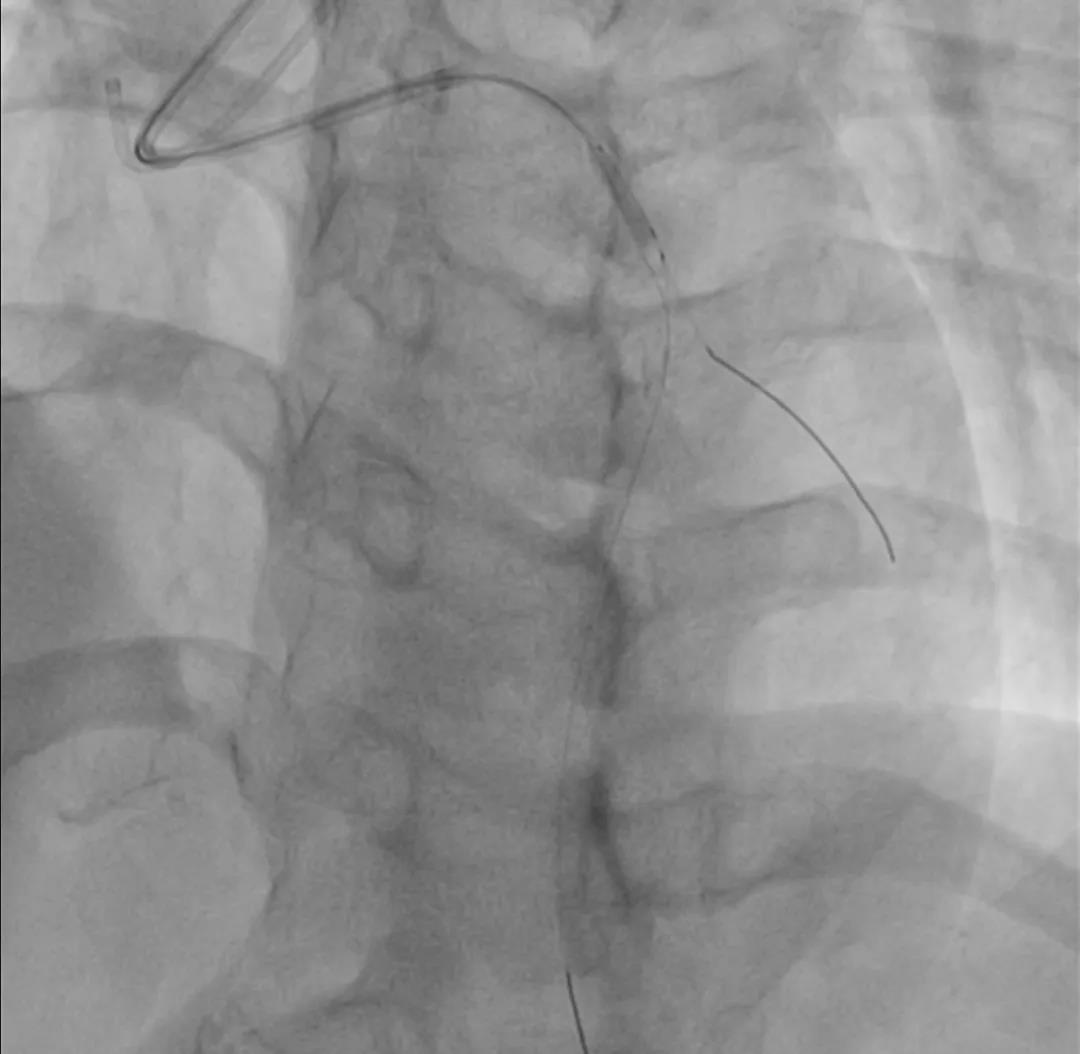

充分预扩

Score flex 2.0*10mm 10atm

Quantum 2.5*20mm 10atm

IVUS-2 预扩张后小夹层和血肿

Dia开口

Dia近段

LAD闭塞段

LAD近段

LAD开口